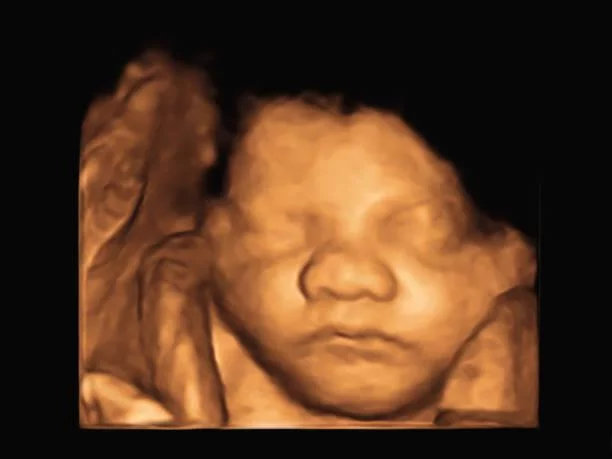

Ultrasound has been developed beyond just the blurry images of the past. Traditionally, it used to show unreadable and unclear images diagnosed in earlier times. But today, thanks to the High-Resolution 3D Imaging technique which has resulted in an amazing outcome. Indeed, by making use of this method 3D ultrasound gives out clear and sharper images enabling doctors to detect the problem with ease. So here’s everything you need to know about 3D Ultrasound Center in Dehradun including its safety, procedure, benefits, and its importance.

The ultrasound technique makes use of high-frequency sound waves to generate images of your internal organ without even making a single cut on your body. It is a non-invasive imaging test that enables you to view soft tissues present in your body. So when you perform 3D ultrasound, the difference in the quality of the image can be seen as it gets enhanced and you are able to see clear, sharp, and realistic images produced with the special imaging software.

So in 3D Ultrasound, the standard 2D Ultrasound images get converted to a volumetric dataset showing excellent high-resolution 3D imaging deducting the dependence on the common ultrasound technique.

3D Ultrasound Imaging is useful in detecting any gynecological health issues related to the infant. It also gives accurate and high-quality images which help to check the problem in-depth.

In prenatal ultrasound services, a 3D Ultrasound is performed on a pregnant lady. It is a test where you get to see your baby for the first time!

Depending on which trimester you get to see the structure of your baby. So it helps to understand your baby’s health and development. In short, to avoid any complications in future and to lessen your worries regarding pregnancy it is always better to perform prenatal care.